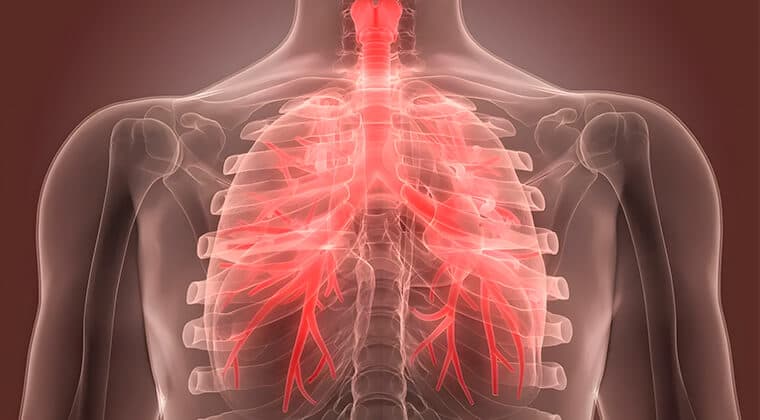

Bronquitis crónica

Inflamación prolongada de las vías respiratorias que causa tos con flema y dificultad para respirar.